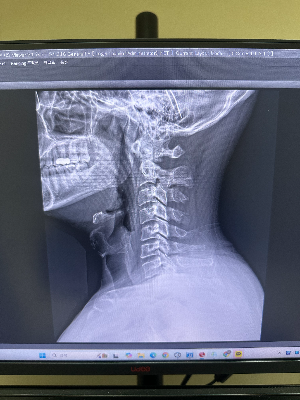

이 무거운 볼링공을 가느다란 목으로 하루 종일 안정적으로 지탱하기 위해, 조물주는 우리의 목뼈를 일직선이 아닌 완만한 곡선 형태로 설계했습니다. 측면(옆)에서 엑스레이를 촬영했을 때, 앞쪽으로 볼록하게 휘어진 이 아름다운 곡선을 의학적 용어로 '경추 전만(Cervical Lordosis)', 흔히 말하는 'C커브'라고 부릅니다.

마치 자동차의 서스펜션(스프링)이나 튼튼한 아치형 다리처럼, 이 C자 형태의 굴곡은 머리의 무게를 분산시키고 걸을 때마다 척추로 전달되는 외부의 충격을 부드럽게 흡수하는 완충 역할을 합니다. 따라서 X-ray 측면 사진에서 7개의 목뼈가 부드러운 C자 모양으로 예쁘게 배열되어 있다면, 뼈와 주변 근육들이 아주 편안한 상태를 유지하고 있다는 뜻입니다.

하지만 컴퓨터 모니터로 빨려 들어갈 듯 고개를 쭉 빼고 일하거나, 고개를 푹 숙인 채 스마트폰을 장시간 들여다보는 잘못된 자세가 반복되면, 목뼈의 배열은 서서히 무너지기 시작합니다. X-ray 측면 사진을 찍어보면 그 변형의 단계를 아주 명확하게 확인할 수 있습니다.

일자목은 말 그대로 완만했던 C자 커브가 사라지고, 7개의 목뼈가 일직선(I자)으로 꼿꼿하게 서 버린 상태를 말합니다. X-ray 사진을 옆에서 보면 마치 자를 대고 그은 것처럼 뼈들이 수직으로 뻣뻣하게 배열되어 있습니다.

군인들이 차렷 자세를 한 것처럼 경직되어 있다고 하여 영어로는 'Military Neck'이라고도 부릅니다. 스프링 역할을 하던 곡선이 사라졌기 때문에, 머리의 무게와 외부 충격이 분산되지 못하고 목뼈와 디스크에 고스란히 전달되기 시작하는 초기 경고 단계입니다.

거북목 환자의 X-ray 측면 사진을 보면, 아래쪽 목뼈(하부 경추)는 앞으로 심하게 과굴곡되어 있고, 위쪽 목뼈(상부 경추)는 앞을 보기 위해 뒤로 젖혀져 있는 아주 기형적인 배열을 보입니다. 어깨선(견봉)을 기준으로 가상의 수직선을 그어보았을 때, 귓불이 그 선보다 2~2.5cm 이상 앞으로 툭 튀어나와 있다면 거북목으로 진단하게 됩니다.

그 직장인 환자분의 엑스레이 사진을 컴퓨터 모니터에 띄우는 순간, 정상적인 C자 곡선은 온데간데없고 뻣뻣한 일자(심지어 역 C자)로 굳어버린 뼈를 보며 저도 모르게 '아이고...' 하는 탄식이 나왔습니다. 진료실에서 원장님께 뼈 때리는 조언을 듣고 나오시며, 수납대 앞에서 쭈뼛쭈뼛 목 스트레칭을 하시던 뒷모습이 아직도 눈에 선하네요.